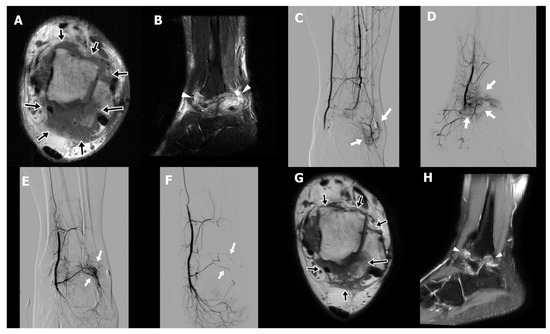

4.2. Ankle Arthrofibrosis Postoperative Case

A 31-year-old male technician (Case 3) presented with chronic right ankle pain and limited plantar flexion persisting for four years following open reduction and internal fixation of an ankle fracture. Despite comprehensive conservative management, including physical therapy, oral NSAIDs, implant removal after fracture healing, and extracorporeal shock wave therapy, his symptoms remained refractory. On physical examination, the patient exhibited hyperalgesia and reported electric-shock-like sensations upon palpation of the posterolateral ankle, indicative of neuropathic pain. MRI demonstrated periarticular fibrotic tissue with increased T2 signal surrounding the tibiotalar joint, particularly in the posterolateral aspect, consistent with arthrofibrosis (Figure 2A,B). An initial attempt at percutaneous needle release of fibrotic tissue combined with prolotherapy was unsuccessful because of intolerable procedural pain. Subsequent diagnostic angiography revealed abnormal angiogenesis involving all three major arterial branches of the lower leg (Figure 2C–E). TAE was performed until complete occlusion of the pathological neovasculature was achieved (Figure 2F). The patient reported early pain relief, with the NRS decreasing from 8 to 5 by the second day following TAE. This improvement allowed for successful and tolerable completion of percutaneous fibrotic tissue needle release in conjunction with dextrose and bone marrow aspirate injections. A second TAE was conducted three months after the initial procedure. Six weeks postintervention, the patient’s NRS further declined to 3, with sustained pain relief observed at both six- and nine-month follow-ups. Follow-up MRI at six months demonstrated a significant decrease in both arthrofibrotic tissue and associated soft tissue edema (Figure 2G,H).

Figure 2. Preprocedural axial T1-weighted magnetic resonance image (MRI) (A) of a 31-year-old male with chronic right ankle pain persisting for 4 years following fracture fixation demonstrates dense fibrotic tissue with intermediate signal intensity along the capsule of the tibiotalar joint, predominantly in the posterolateral aspect (arrows in (A)). The sagittal T2-weighted fat-suppressed image (B) reveals heterogeneous high signal intensity consistent with a diffuse inflammatory process (arrowheads in (B)). Selective digital subtraction angiography (DSA) of the peroneal artery (anterior–posterior projection (C)), posterior tibial artery (lateral projection (D)), and anterior tibial artery (anterior–posterior projection, (E)) demonstrates abnormal angiogenesis (arrows in (CE)) corresponding to the patient’s area of maximal pain, which is marked externally by a circular skin marker. Post-embolization angiography of the anterior tibial artery (F) shows resolution of the abnormal vascular blush (arrow in (F)) while preserving normal arterial branches. Follow-up MRI at 6 months reveals decreased fibrotic tissue in the posterolateral tibiotalar joint capsule on axial T1-weighted imaging (arrows in (G)), and reduced T2 hyperintensity on sagittal imaging (arrowheads in (H)), indicating regression of inflammation compared with baseline.